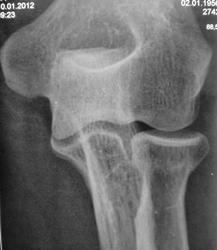

Травма. Пациент направлен на рентгенографию локтевого сустава.

Пациент направлен на рентгенографию локтевого сустава.

Перелом шейки луча без смещения.